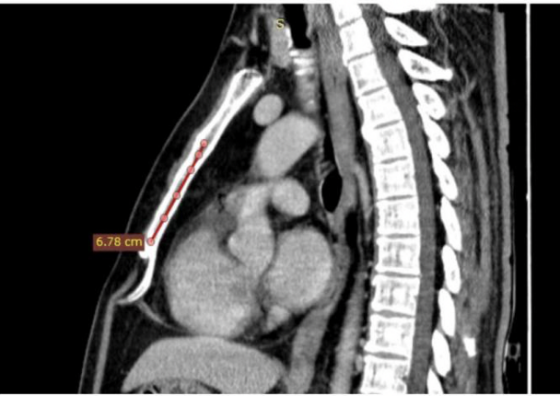

然而术前评估遭遇挑战:患者胸部 CT 显示心脏位置偏低,胸骨长度仅 7 cm,而该设备胸骨后电极所需空间通常为 9 cm。美国同行及技术支持人员均对此表示顾虑并持否定态度。俞建华教授团队联合本院心脏大血管外科杨威教授,反复进行解剖位置分析,广泛参考国内外临床经验,与美方技术人员多轮沟通论证,最终确定了电极的安全植入路径。

手术中,团队经剑突下及左侧腋中线切口,精准分离腹直肌鞘与膈肌薄弱点,将除颤线圈精确置入胸骨后左缘、心包膜前缘,电极经皮下隧道连接至左侧腋中线 ICD 装置。术中诱颤测试显示,30J 能量一次除颤成功转复,程控测定 R 波振幅达 5.3mV,各项参数均符合标准。据了解,该病例是目前国内已知胸骨最短的 EV-ICD 植入患者,手术难度极具挑战性。